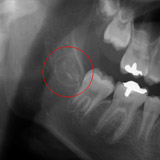

X線写真の赤丸で囲んだ部分が第3大臼歯(親知らず)の歯胚です。

歯胚摘出として骨を削らずに取り出せるのはこの段階(stage2)までです。

これ以上歯が大きくなると骨を削ってとる抜歯になります。